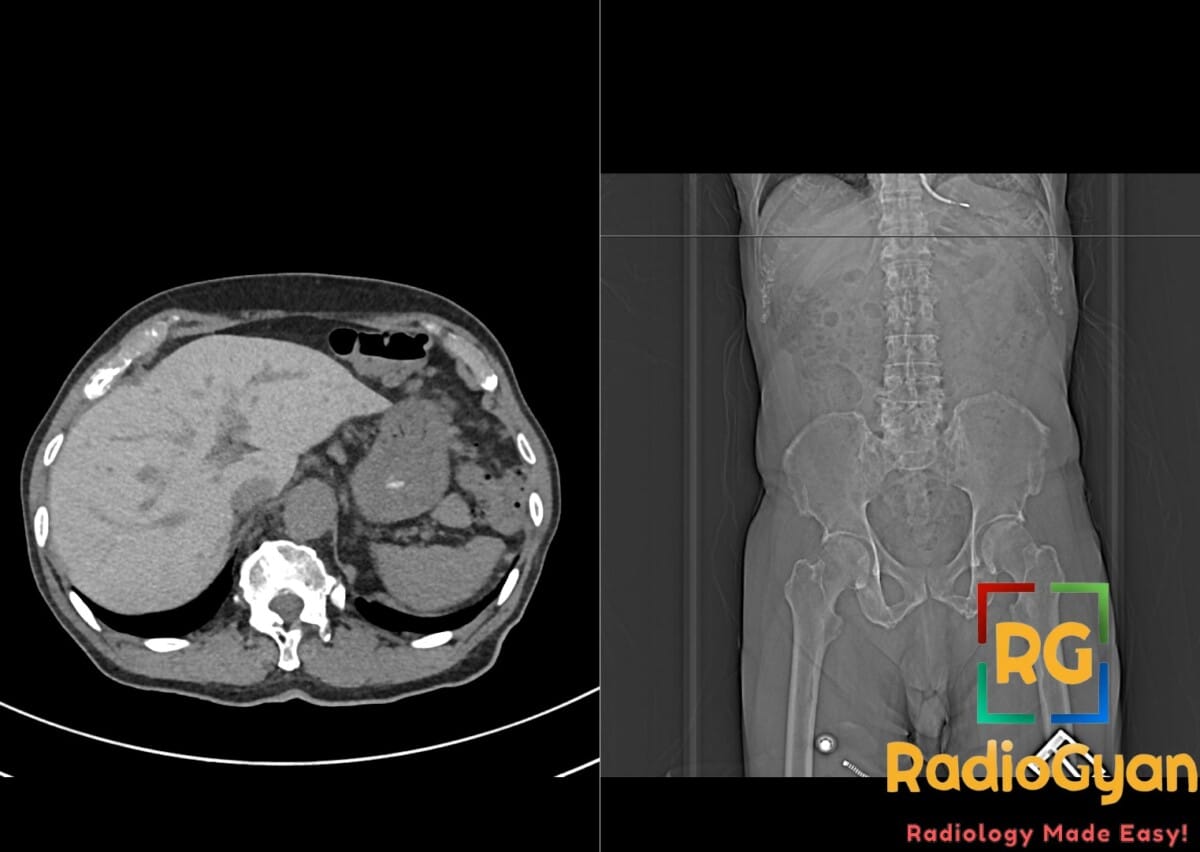

CT scan showing hyperdense liver in a patient on Amiodarone, indicating drug-induced toxicity effects.

Hyperdense liver on CT scan due to Amiodarone therapy. Notice the ICD device overlying the heart on the frontal scout image.

• CT: Markedly increased liver parenchymal attenuation (hyperdense liver), often >90-150 HU on non-contrast scans; liver density significantly exceeds spleen density (normal liver/spleen ratio ~1-1.3); hyperattenuation due to iodine content, seen without IV contrast